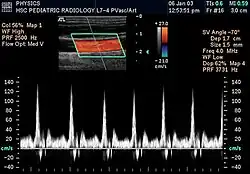

Спектральная доплерография

Предназначена для оценки движения подвижных сред. В частности, кровотока в относительно крупных сосудах и камерах сердца, стенок сердца. Основным видом диагностической информации является спектрографическая запись, представляющая собой развертку скорости кровотока во времени. На таком графике по вертикальной оси откладывается скорость, а по горизонтальной — время. Сигналы, отображающиеся выше горизонтальной оси, идут от потока крови, направленного к датчику, ниже этой оси — от датчика. Помимо скорости и направления кровотока, по виду доплеровской спектрограммы можно определить характер потока крови: ламинарный поток отображается в виде узкой кривой с четкими контурами, турбулентный — широкой неоднородной кривой.